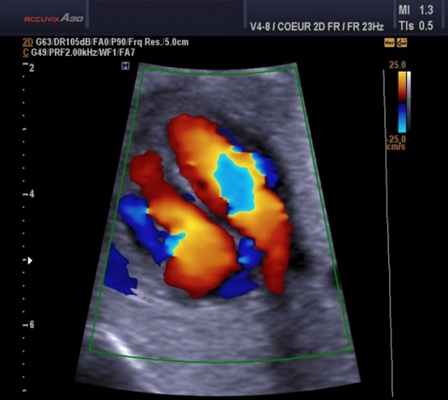

CFM (CDI, CDV, CD, CF, ЦДК и т.д.) – режим цветового допплеровского картирования по скорости

В режиме цветового допплеровского картирования по скорости (ЦДК) изображение строится также как и в B-режиме. Отличительной особенностью режима ЦДК является цветовое отображение информации о скорости и направлении движения структур в выделенной пользователем области (окно опроса). Режим ЦДК обладает ярко выраженной зависимостью от величины допплеровского угла.

Для облегчения выявления турбулентного движения (завихрений) существует порог скорости, выше которого происходит изменение цвета (во многих аппаратах это зелены). «Мозаичный» узор на участке турбулентного потока позволяет легко установить регургитацию (смену направления движения), что помогает определить степень недостаточности клапанов.

Так, например, эхокардиография с допплерометрией и цветным допплеровским картированием (ЦДК), которая является сочетанием 2D и М-режимов с допплерометрией, очень полезна при оценке митрального стеноза. Первые два способа визуализации позволяют заподозрить кальцификацию клапана (аномальное движение его створок).

Допплерометрия демонстрирует при этой патологии повышенную скорость кровотока (признак сужения) и может быть использована для оценки «эффективной площади отверстия» (степени выраженности стеноза).